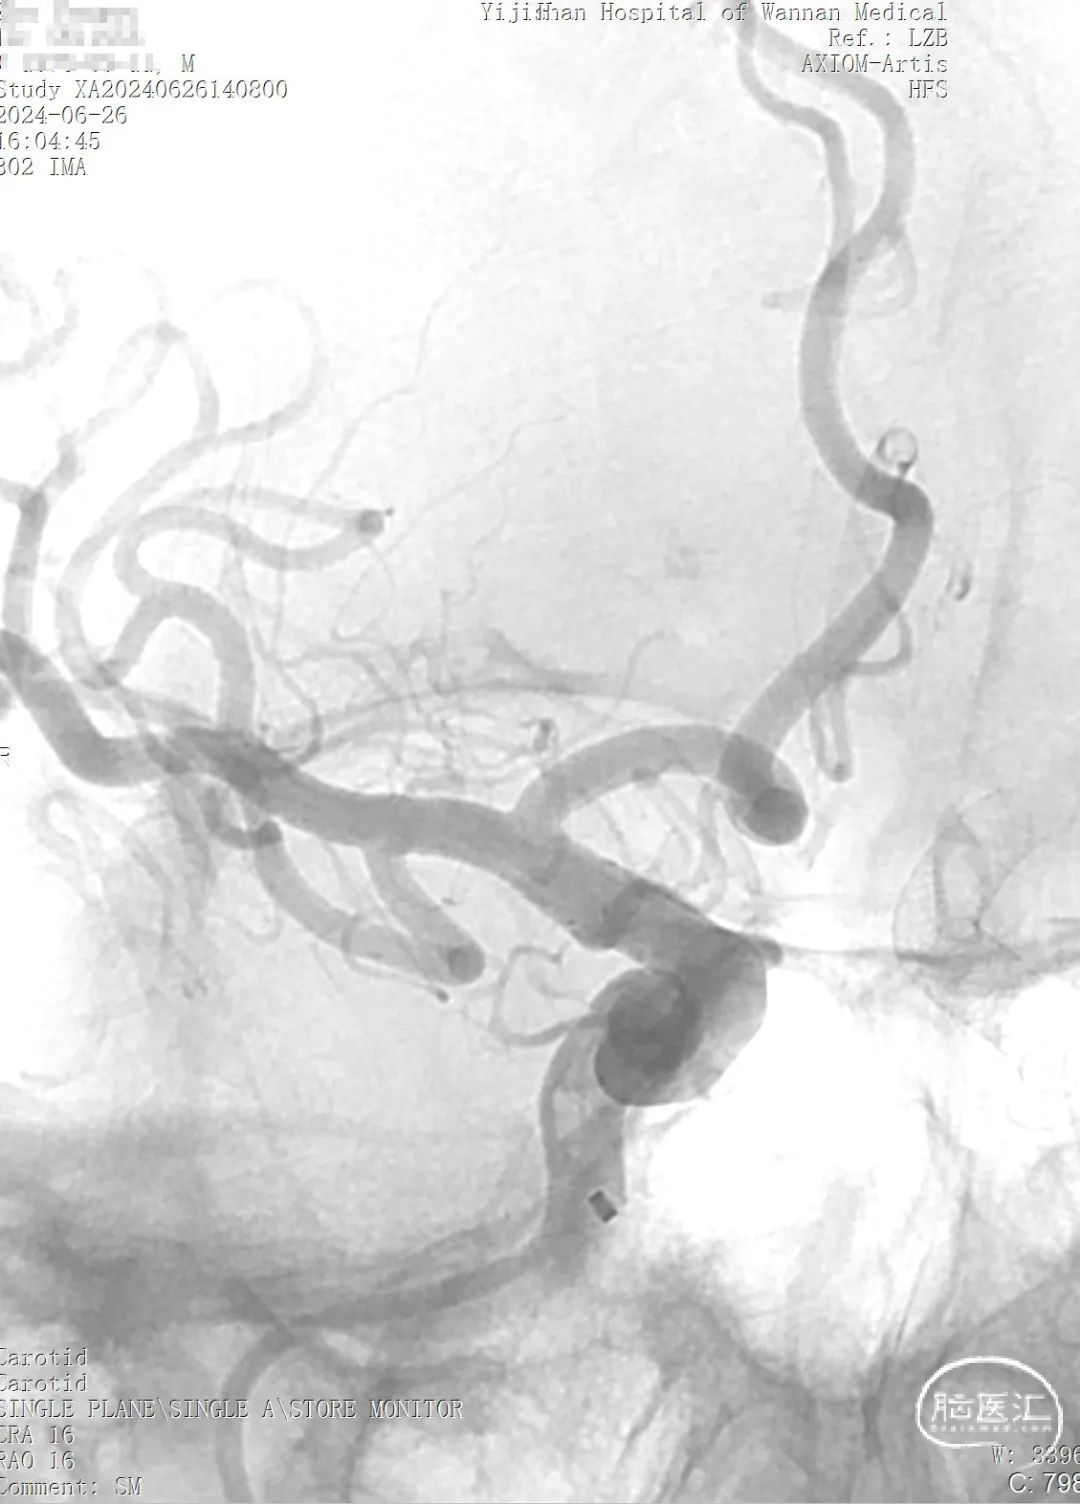

➢ 术前造影

通桥麒麟™血流导向密网支架成功释放。

通桥麒麟™血流导向密网支架完全释放,术后造影。

术后血管造影见动脉瘤仍有显影,瘤腔内造影剂滞留,支架展开,贴壁良好,载瘤血管血流通畅,手术顺利。